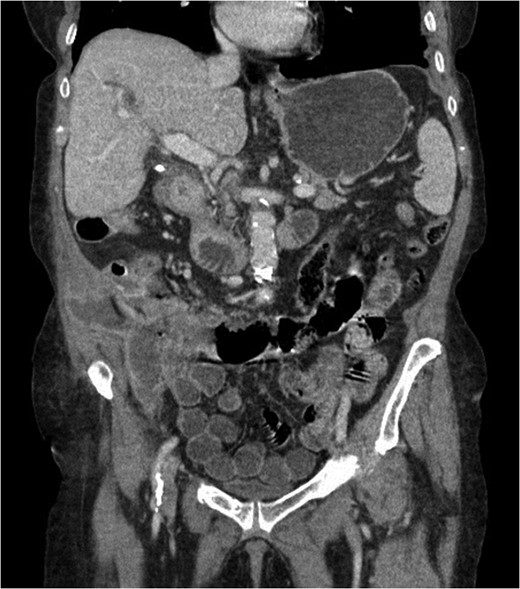

At presentation her vital signs were stable. Abdominal exam revealed exquisite tenderness in the right lower quadrant, with no evidence of digital clubbing. Blood-work revealed an elevated WBC of 15.6. A CT scan demonstrated a 4.3 cm annular mass within the cecum, suspicious for a primary colonic malignancy, as well as an 8.6 × 8.2 cm2 lobulated gas-containing abscess with extension in to the lateral abdominal wall (Figs 4 and 5).

Coronal view of abdominal CT scan showing cecal mass with evidence of perforation.